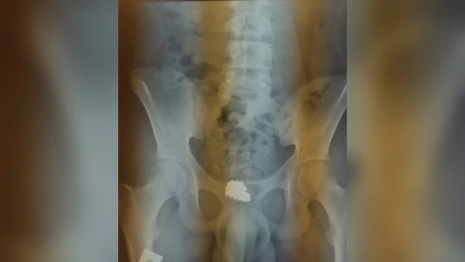

В отделении диагноз подтвердили. Пациенту провели цистотомию. Инородные тела (46 шариков) удалили.